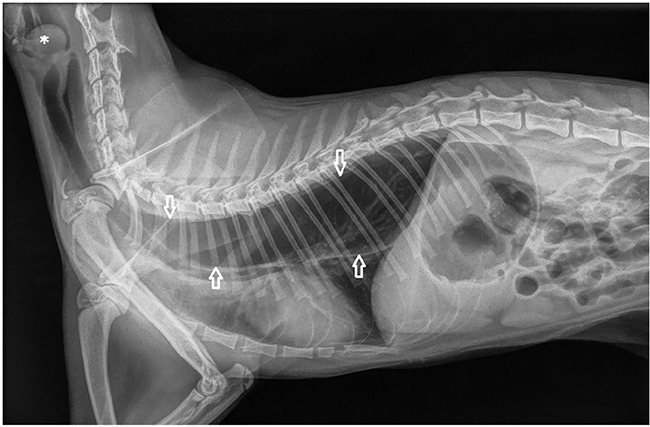

Case summary: An 8-month-old spayed female cat presented with a 7-week history of progressive dyspnoea, dysphagia and regurgitation. Plain radiography revealed megaoesophagus with a large, rounded, soft tissue opacity laryngeal mass. Endoscopic examination revealed a fluid-filled lesion, which was lanced and drained completely. As a result of recurrence of the mass and infection 2 days later, the mass was surgically excised. The mass was diagnosed as a laryngomucocele based on clinical and histopathological findings. Clinical signs resolved immediately after removal of the mass, the megaoesophagus resolved a couple of days postoperatively and no relapse was noted over the following 3 years.